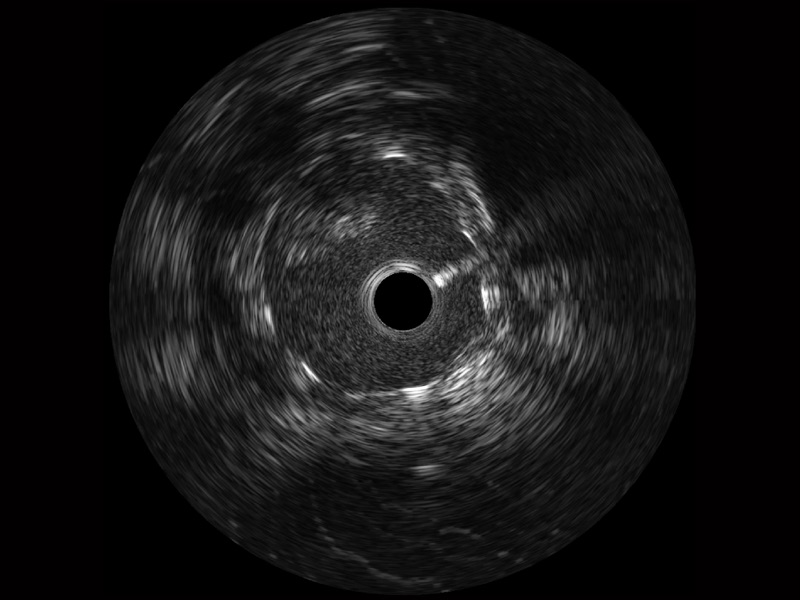

传统IVUS图像

对比传统IVUS导管成像,玖鼎集团宽频IVUS图像的近场支架梁显影更细腻,远场中膜外血管仍清晰可辨,兼顾远中近,兼顾分辨力与穿透深度